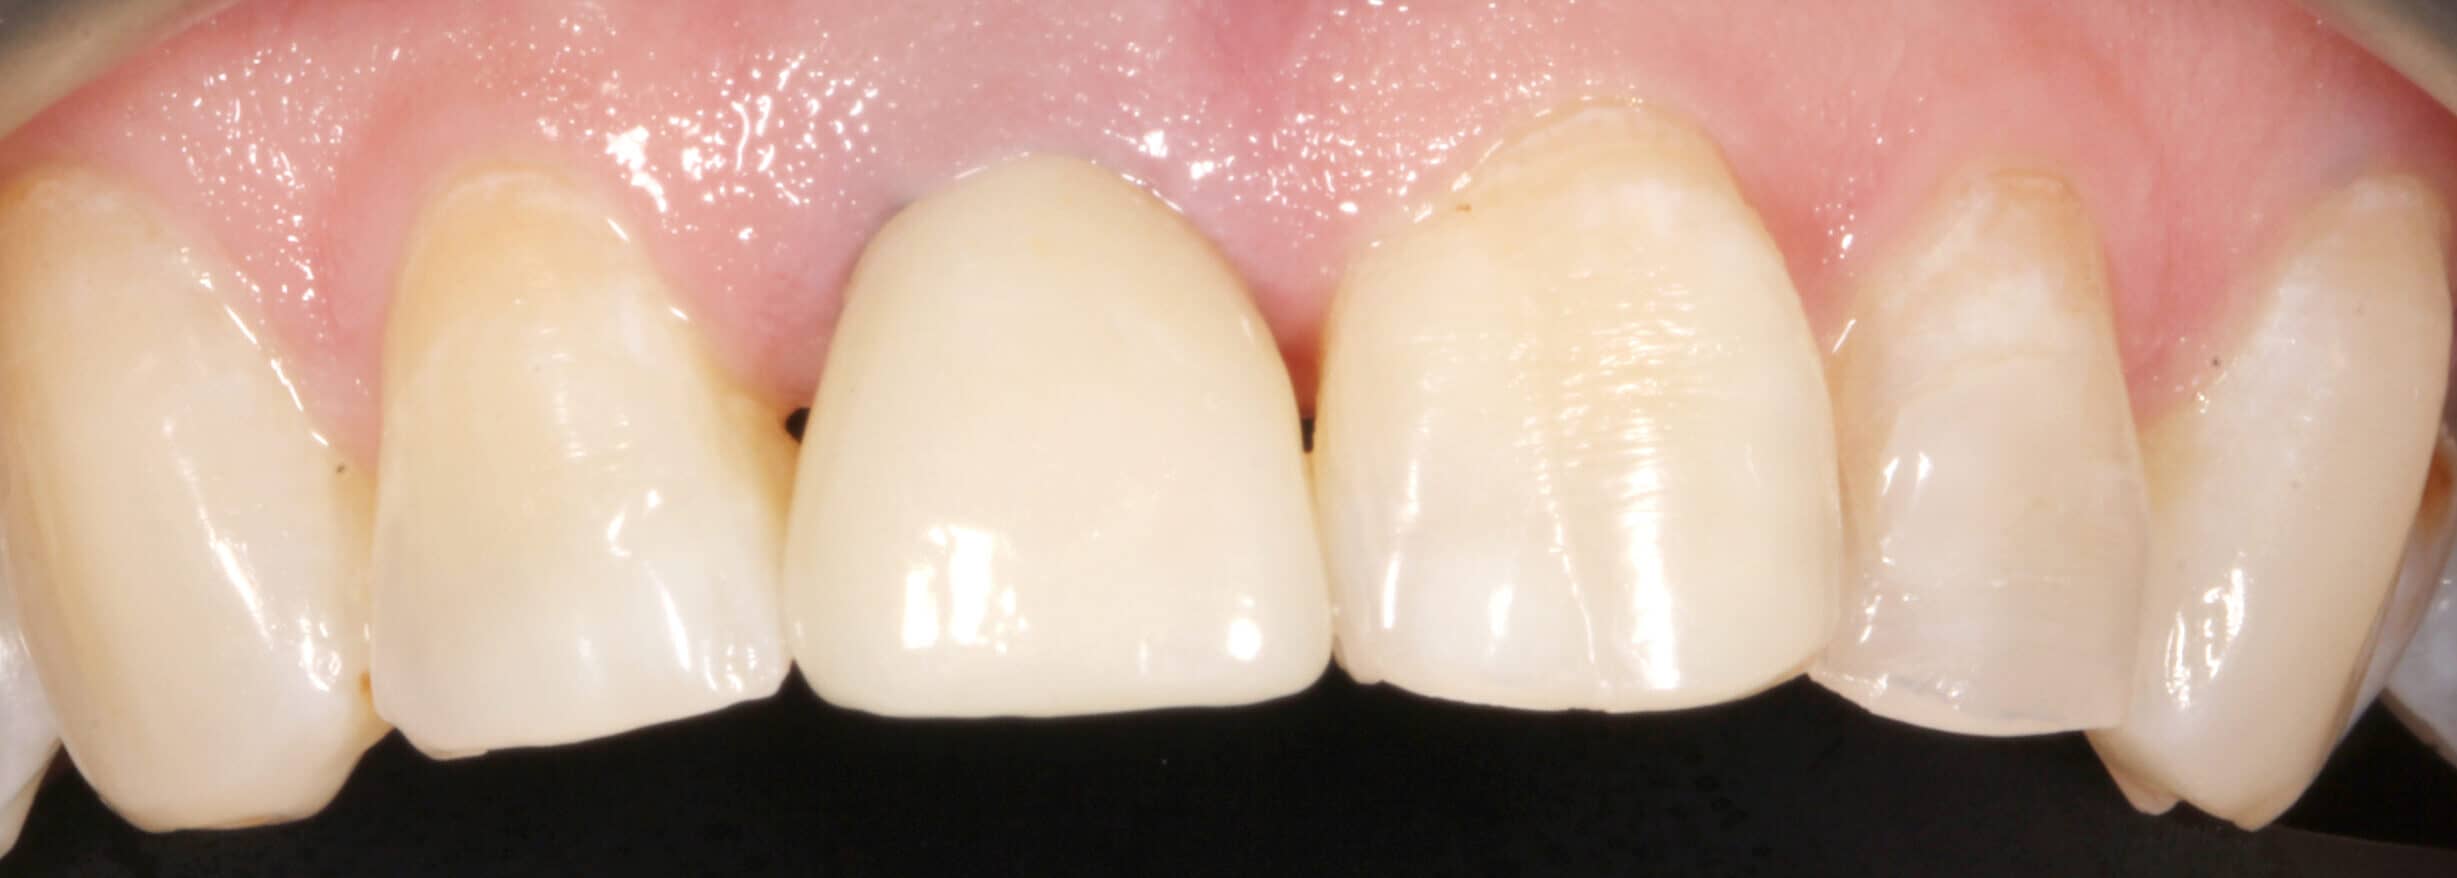

Porcelain crowns are custom crafted by a masterful technician. The work requires artistic talent and takes years to master.

Our master lab technician crafted a beautiful porcelain crown to cement on top of the patient’s root canal and rescue post. Once the crown was cemented it blended in with his natural teeth beautifully.